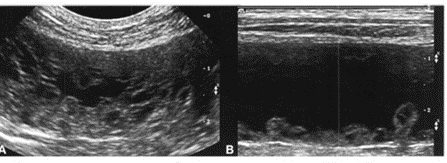

1. Ультразвуковое исследование (УЗИ) — "золотой стандарт" диагностики. Врач видит характерные изменения: матка увеличена, ее стенки утолщены, а в структуре эндометрия видны множественные анэхогенные (темные) кисты.